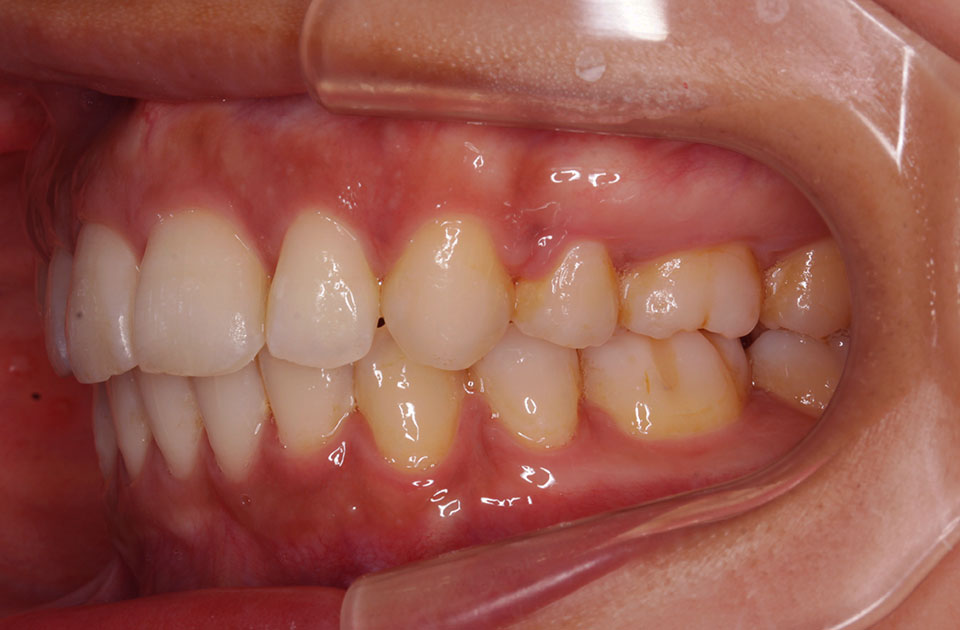

矯正前 右側

主訴 口元の突出感を治したい。ガミースマイルを治したい。

年齢 20代

治療法 上下顎マルチブラケット装置

抜歯の有無 上顎左右側第一小臼歯、下顎左右側第一小臼歯

治療期間 1年10ヶ月